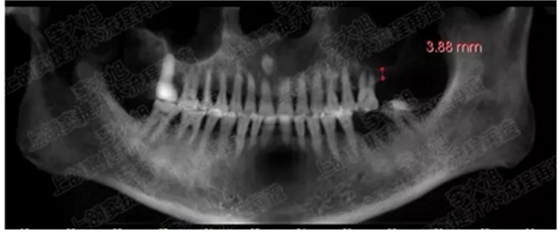

病例二

剩余骨量2mm

003.png

提升10mm

004.png

病例三

剩余骨量3mm

005.png

006.png